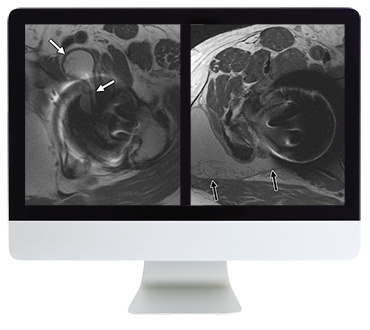

ARRS Controversies In Hip And Pelvis Imaging 2016 (CME VIDEOS) This Online Course provides established principles and new concepts regarding pathology of the hip and pelvis, with an emphasis on MRI. Lectures cover a number of clinically important topics, including pitfalls and postoperative findings essential to the practicing radiologist.

- recognize the concept of femoroacetabular impingement and its implications on patient care

- identify acetabular labral tear on MRI with improved confidence

- Conundrums in Hip Imaging–Kirkland Davis, MD

- Controversies and Challenges in Imaging Femoroacetabular Impingement (FAI)–Michael Recht, MD